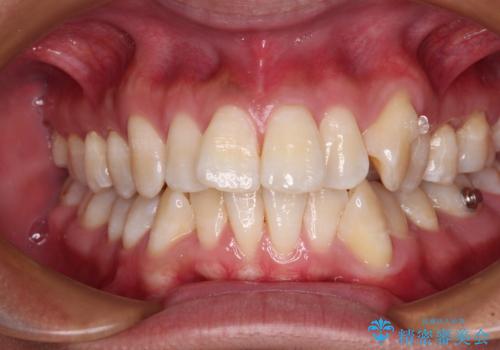

- 八重歯と飛び出している前歯を気にして来院された患者様です。

歯列としてはインビザラインでもワイヤー矯正でも対応できるものでしたが、上顎の八重歯や下顎小臼歯の捻転といったインビザラインでは時間のかかってしまう歯列不正が認められたため、補助装置やワイヤー矯正を治療当初に使用することで、インビザラインによる治療をスムーズに行えるように計画しました。